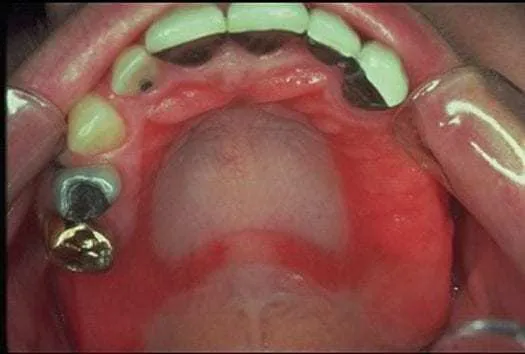

Pierwsze sygnały alarmowe alergii na nikiel w jamie ustnej często są subtelne i łatwe do zignorowania lub pomylenia z innymi problemami. Pacjenci często zgłaszają uczucie pieczenia języka, warg, dziąseł, a nawet całego podniebienia. Nierzadko towarzyszy temu utrzymujący się, nieprzyjemny metaliczny lub gorzki posmak w ustach, który nie ustępuje po szczotkowaniu czy płukaniu. Dodatkowo, wielu pacjentów doświadcza suchości w ustach (kserostomii), co jest wynikiem zmniejszonej produkcji śliny. W miarę rozwoju reakcji alergicznej mogą pojawić się bardziej widoczne zmiany. Obserwuję u pacjentów wyraźne zaczerwienienie i obrzęk błony śluzowej w miejscach bezpośredniego kontaktu z metalem na przykład pod protezą, wokół zamków aparatu ortodontycznego czy w pobliżu korony. Charakterystyczne są również reakcje liszajowate, czyli białe, siateczkowate zmiany na błonie śluzowej policzków, które mogą przypominać liszaj płaski. Czasami alergia manifestuje się także jako zapalenie kącików ust (zajady), czyli bolesne pęknięcia i stany zapalne. Alergia na nikiel może również wpływać na język i dziąsła w sposób specyficzny. Na języku może rozwinąć się zapalenie języka (glossitis), objawiające się jego wygładzeniem, zaczerwienieniem, bólem, a nawet utratą smaku (ageuzją). Dziąsła natomiast mogą reagować nieropnym zapaleniem (gingivitis), które, co istotne, nie ustępuje pomimo wzorowej higieny jamy ustnej. To jest dla mnie ważny sygnał, że problem może leżeć głębiej niż w niedostatecznej pielęgnacji. W przypadku noszenia aparatu ortodontycznego, objawy alergii na nikiel mogą być mylące, ponieważ początkowy dyskomfort jest typowy. Kluczowe jest jednak odróżnienie normalnych dolegliwości (np. ból po aktywacji aparatu, otarcia) od objawów alergicznych. Te drugie często manifestują się w bezpośrednim kontakcie z metalem, są uporczywe, utrzymują się długo i, co najważniejsze, nie ustępują pomimo prawidłowej higieny i adaptacji do aparatu. Jeśli zauważasz, że pieczenie, zaczerwienienie czy metaliczny posmak utrzymują się tygodniami, a nawet miesiącami, to jest to silny sygnał, by skonsultować się ze specjalistą.Od podejrzeń do pewności: profesjonalna diagnostyka alergii na nikiel